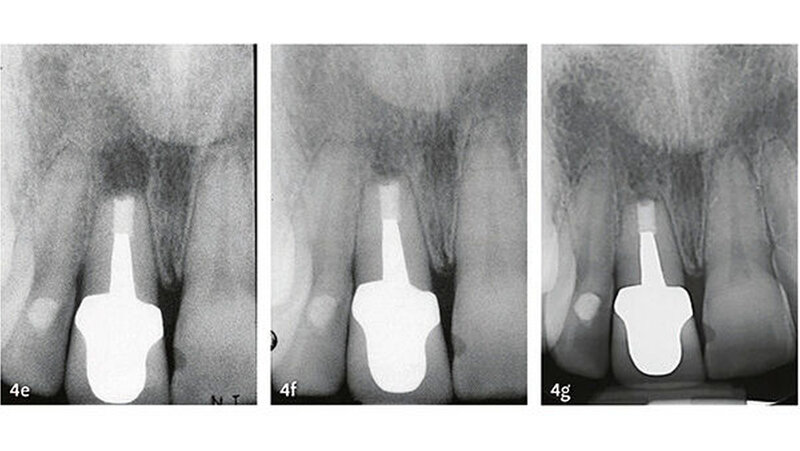

Klinische Studien

Die wesentlichen Daten von klinischen Studien über die Anwendung von MTA als retrogradem Füllmaterial sind in Tabelle III zusammengefasst. Die erste klinische Studie mit Auswertung der Erfolgsrate nach MTA-Anwendung in der apikalen Chirurgie wurde von Chong et al. (2003) publiziert - es war auch gleich die erste randomisierte Studie, welche MTA mit einem anderen retrograden Verschlusszement untersucht hat. Generell zeigen alle klinischen Studien sehr hohe Erfolgsraten für MTA in der apikalen Chirurgie (83,7% bis 96%). Die von uns 2014 publizierten Langzeitdaten (5 Jahre Beobachtungsdauer für alle behandelten Zähne) mit einer Erfolgsrate von 92,5% deuten auf eine sehr gute Stabilität und auf ein hohes Abdichtungsvermögen von MTA (von Arx et al. 2014) (Abb. 4 und 5).

Die Dokumentation der 10-Jahresdaten ist im Gange, und die bisherige Analyse deutet auf eine konstant hohe Erfolgsrate auch nach zehn Jahren (Abb. 6). Eine systematische Auswertung mit Meta-Analyse aller bis 2007 publizierten retrograden Füllmaterialien in Vergleichsstudien mit mindestens zwei getesteten Verschlussmaterialien ergab für MTA die höchste Wahrscheinlichkeit einer periapikalen Ausheilung (91,4%) (von Arx et al. 2010a).